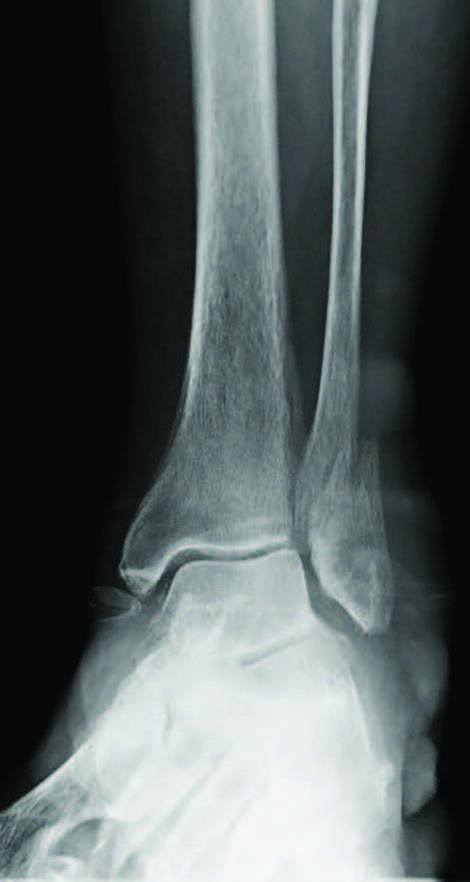

Ankle fractures are common orthopedic injuries, accounting for approximately 20 percent of lower extremity trauma.1 Of these fractures, greater than 50 percent are relatively predictable in that the etiology is a supination-external rotation-type mechanism.2 When these injuries are unstable (ie deltoid ligament rupture, medial malleolar avulsion fracture, syndesmotic involvement, posterior malleolar involvement), open reduction and internal fixation (ORIF) is an option to achieve realignment of the ankle mortise back to its original anatomic state.1 Proper preoperative planning and surgical technique are essential considerations for optimal osseous healing and return to normal function; however, determining postoperative protocols such as immobilization duration and weight-bearing status are also important. A contemporary question when considering these injuries is if there is compromise of osseous bridging when initiating early weight-bearing. Or, does it simply aid in an earlier return to normal activities without compromised healing? In this submission, we aim to discuss the normal biomechanics and kinetics of the ankle joint and attempt to critically evaluate the medical literature comparing traditional versus early weight-bearing protocols following ankle fracture ORIF.

When considering bipedal motion, it is clearly important to understand the role of the ankle joint in sagittal plane motion at the junction of the foot and the leg.3 The ankle joint includes the tibia and fibula’s distal articular surfaces and the talus’s trochlear surface. The talus is broader anteriorly than posteriorly and is depressed centrally, which corresponds to the articular surface of the distal tibia.3 The malleoli reside medial and laterally to the talar body. The lateral malleolus position is more posterior and distal than the medial malleolus, which corresponds to the ankle joint axis. These periarticular surfaces gain support from the medial and lateral collateral ligaments, which stabilize and limit available sagittal plane range of motion.3

The oblique nature of the ankle joint also allows some transverse and frontal plane motions, again corresponding to the angular deviation of the malleoli. This axis will deviate plantar-medially with plantarflexion and plantar-laterally with dorsiflexion. Again, the axis parallels the position of the malleoli with approximately 10 to 30 degrees of dorsiflexion.3 When the foot is in open-chain kinetics, the primary movement will occur in the sagittal plane with associated abduction with dorsiflexion and adduction with plantarflexion. The stability of the joint surfaces strongly depends on ligamentous integrity. If there is excessive laxity or injury, there will be a shift in the ankle joint’s axis of rotation and movement.3